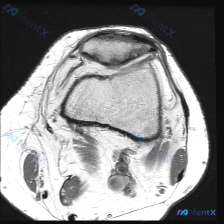

最近碰到一个有意思的读片病例,临床怀疑膝关节软骨异常,给了一张髌股关节轴位T1加权MRI,整理了一下分析思路分享给大家。 一、病例基本影像信息 这是单张膝关节髌股关节水平的轴位T1加权MRI扫描图: 1. 扫描层面:髌股关节水平,可见上方髌骨、下方股骨滑车沟的关节结构 2. 骨骼:股骨远端骨皮质完整...

大家好,今天分享一个非常有临床意义的读片病例,核心矛盾点很值得讨论。 病例基本信息 本病例提供了膝关节MRI T1序列轴位髌股关节层面影像,临床提示存在软骨异常,要求读片分析。 影像学所见 本次扫描层面为髌股关节层面,影像可见: 1. 髌骨、股骨髁关节软骨:髌骨后方软骨连续光滑,股骨滑车软骨厚度均匀...

今天看到一个很有代表性的读片问题,整理出来和大家分享讨论。 病例基础信息 这是一张膝关节MRI T2序列轴位图像,临床提问是:图像中是否存在可识别的软骨异常? 影像阅片结果 先给大家整理一下这张图像的客观观察: 1. 解剖层面:髌股关节层面,显示髌骨、股骨滑车沟及周边软组织结构 2. 骨骼结构:髌骨...

刚整理了一个很有代表性的读片病例,临床怀疑膝关节软骨异常,只提供了一张膝关节MRI轴位T1加权图像,分享一下完整分析思路,大家一起讨论。 病例影像基本信息 本次仅提供单张膝关节MRI轴位T1加权图像,影像学观察结果如下: 1. 骨骼结构:髌骨、股骨髁骨皮质连续,未见明显骨折线,骨髓信号符合正常T1加...